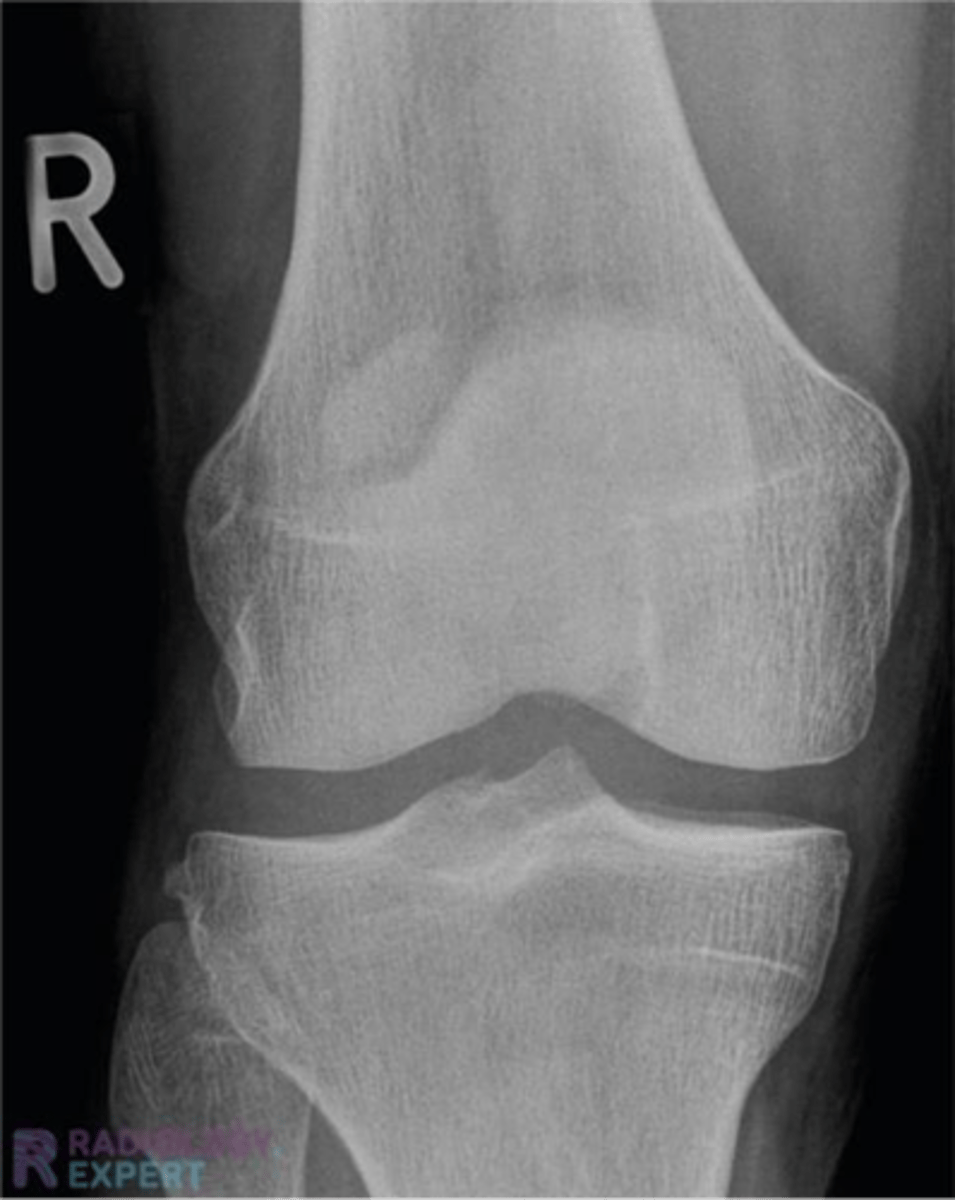

what does this x-ray show

something is wrong with the soft tissue

x-ray

shows us things with high levels of calcium

magnetic resonance imaging (MRI)

shows us bones and soft tissues (diagnostic modality of choice for soft tissue and thus the knee)